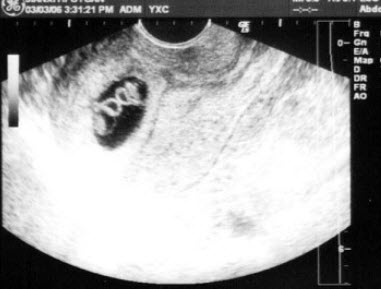

女,26岁,停经3个月,HCG阳性。根据B超检查声像图如下,最可能的诊断为()

A.葡萄胎

B.子宫肌瘤

C.稽留流产

D.不全流产

E.绒癌